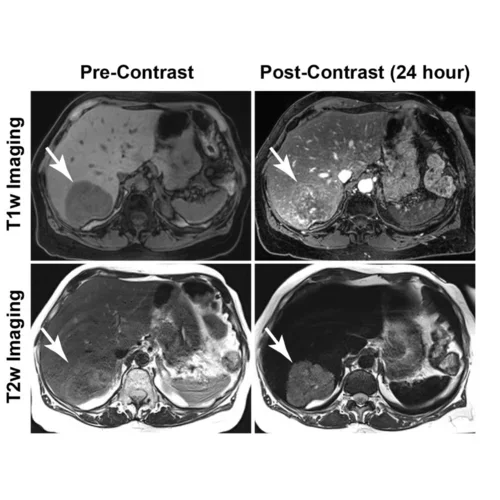

- Quantitative prostate MRI

- Quantitative liver MRI and MRE